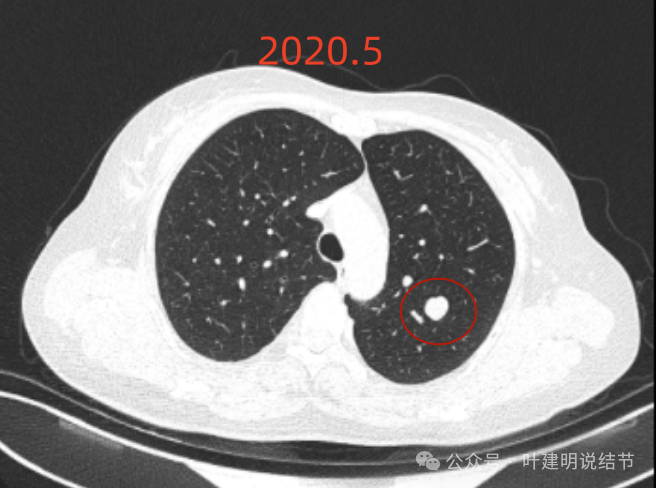

2020年5月,病灶仍是边缘非常光滑,局部表面似有凹陷。